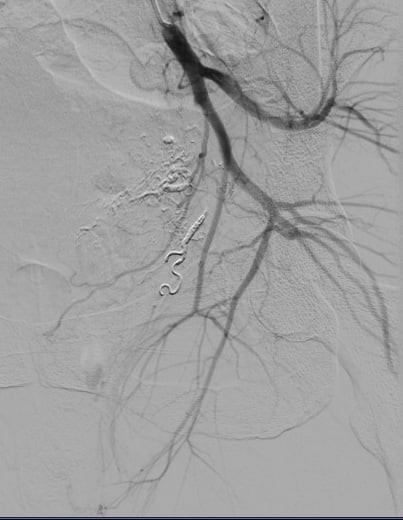

sau nút mạch quanh động mạch trực tràng

Sau 90 phút cân não, bằng tất cả trí lực và hệ thống trang thiết bị hiện đại, kíp bác sĩ Trung tâm Điện quang đã làm nên kỳ tích trong lịch sử điện quang can thiệp Việt Nam. Nhớ lại khoảnh khắc “đấu trí” với tử thần đó, BSCKII. Phan Hoàng Giang, người trực tiếp thực hiện ca can thiệp cho biết: “Đây là lần đầu tiên, chúng tôi gặp trường hợp chảy máu sau đẻ mà nguồn gốc lại từ động mạch mạc treo tràng dưới. Ca lâm sàng này rất hiếm gặp trên thế giới. Ca được báo cáo lần đầu tiên là vào năm 2015. Và trong một nghiên cứu lên đến 783 bệnh nhân thì chỉ có 8 bệnh nhân mắc (chiếm 1% các trường hợp chảy máu sau đẻ). Với những bệnh nhân đã cắt tử cung càng khó khăn trong quá trình tìm động mạch tử cung nhằm cầm máu và gây tắc. Ca sản phụ này khá phức tạp và mất nhiều thời gian hơn so với ca chảy máu sau đẻ thông thường. Bình thường, chúng tôi chỉ gây tắc nhánh mạch tổn thương và cầm máu tạm thời động mạch chậu trong hai bên. Tuy nhiên với bệnh nhân này, chúng tôi cần tìm thêm các nhánh chảy máu quanh trực tràng, gồm 6 nhánh mạch 2 bên: động mạch trực tràng trên, động mạch trực tràng giữa và động mạch trực tràng dưới. Sau khi xác định được nhánh chảy máu, chúng tôi phải lựa chọn vật liệu gây tắc mạch cũng như vị trí can thiệp để không bị hoại tử trực tràng”. Sau 36 tiếng theo dõi an toàn, sản phụ đã được xuất viện, trở về nhà cùng chồng và 3 con thơ.